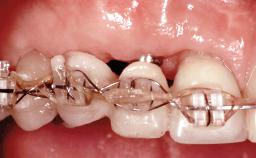

This 20-year-old woman was referred to our department in July 2006. Four months earlier, she had experienced dental trauma to the anterior maxilla when traveling in South America. The emergency treatment included emergency root canal treatment of teeth 12 and 11. Tooth 21 was also subjected to endodontic treatment later. At the initial examination, the patient was not in pain but reported increased mobility of tooth 12. The clinical examination revealed a high smile line, medium thickness of the soft tissue, and rectangular tooth forms. Discoloration of tooth 12 was evident. The periapical radiograph provided by the referring dentist indicated a fracture line at both teeth 12 and 11. A cone-beam computed tomography (CBCT) scan confirmed these fractures. No pathology was found to be associated with tooth 21.